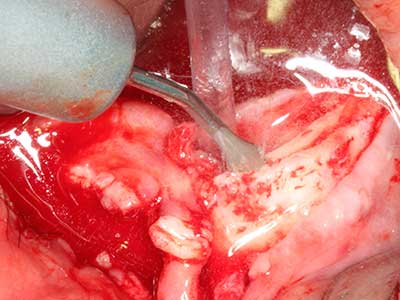

Si es preciso realizar intervenciones quirúrgicas en las que el hueso está en contacto directo con estructuras sensibles, como son los vasos sanguíneos o los nervios, los instrumentos rotativos presentan un enorme potencial de provocar lesiones iatrogénicas. Así, precisamente en la representación de nervios después de una lesión iatrogénica, o en el transcurso de la lateralización de un nervio para resecciones, reconstrucciones o incorporación de implantes, los equipos piezoeléctricos pueden resultar muy útiles para preparar la tapa ósea y retirar las partes de tejido duro cercanas al nervio (fig. 17-20). Por lo general, un ligero contacto del cordón nervioso con el inserto piezoeléctrico no tiene consecuencia alguna; ahora bien, un procedimiento poco cuidadoso con movimientos tipo sierra o piezas de trabajo sobre la base ósea aún existente puede provocar lesiones nerviosas temporales o incluso permanentes. Con todo, el riesgo de sufrir una lesión de este tipo se considera significativamente inferior que en los casos en los que se utilizan sierras y fresas (Pereira, Gealh et al. 2014).